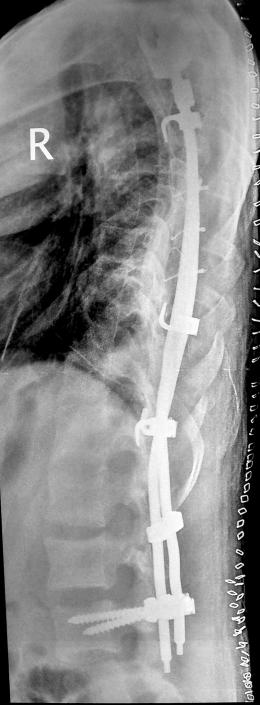

Post operative X-rays standing erect PA & Lateral, after 10 days of surgery. Clinical picture after a month. Segmental fixation with hooks, pedical screws & rods.

Post-op

Post op Xray